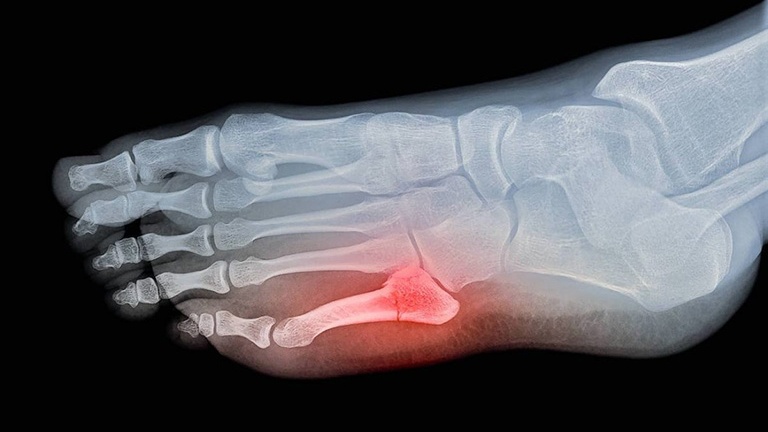

Khi nhận biết được những dấu hiệu không bình thường này ở bàn chân, bạn cần đến các cơ sở y tế chuyên khoa Cơ xương khớp ngay lập tức để được bác sĩ thăm khám và chẩn đoán kỹ lưỡng. Thông qua quá trình kiểm tra lâm sàng và các phương pháp chẩn đoán như X-quang, bác sĩ sẽ xác định chính xác vị trí và mức độ của gãy xương. Từ đó, đưa ra phương pháp điều trị thích hợp nhất, giúp bạn phục hồi nhanh chóng và hiệu quả.

Gãy xương bàn chân số 5 bó bột bao lâu có thể khác nhau tùy thuộc vào nhiều yếu tố như độ nghiêm trọng của chấn thương, tuổi tác, sức khỏe tổng thể và liệu pháp điều trị được áp dụng. Tuy nhiên, trong trường hợp phổ biến, việc bó bột xương bàn chân số 5 thường kéo dài từ 6 đến 8 tuần để cho xương lành lại.